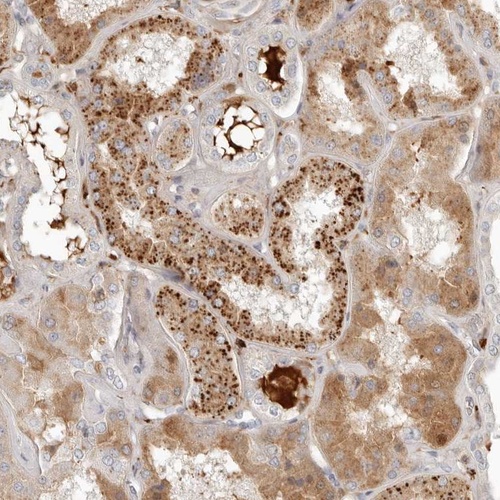

Immunohistochemical staining of human kidney shows strong granular positivity in tubular cells.